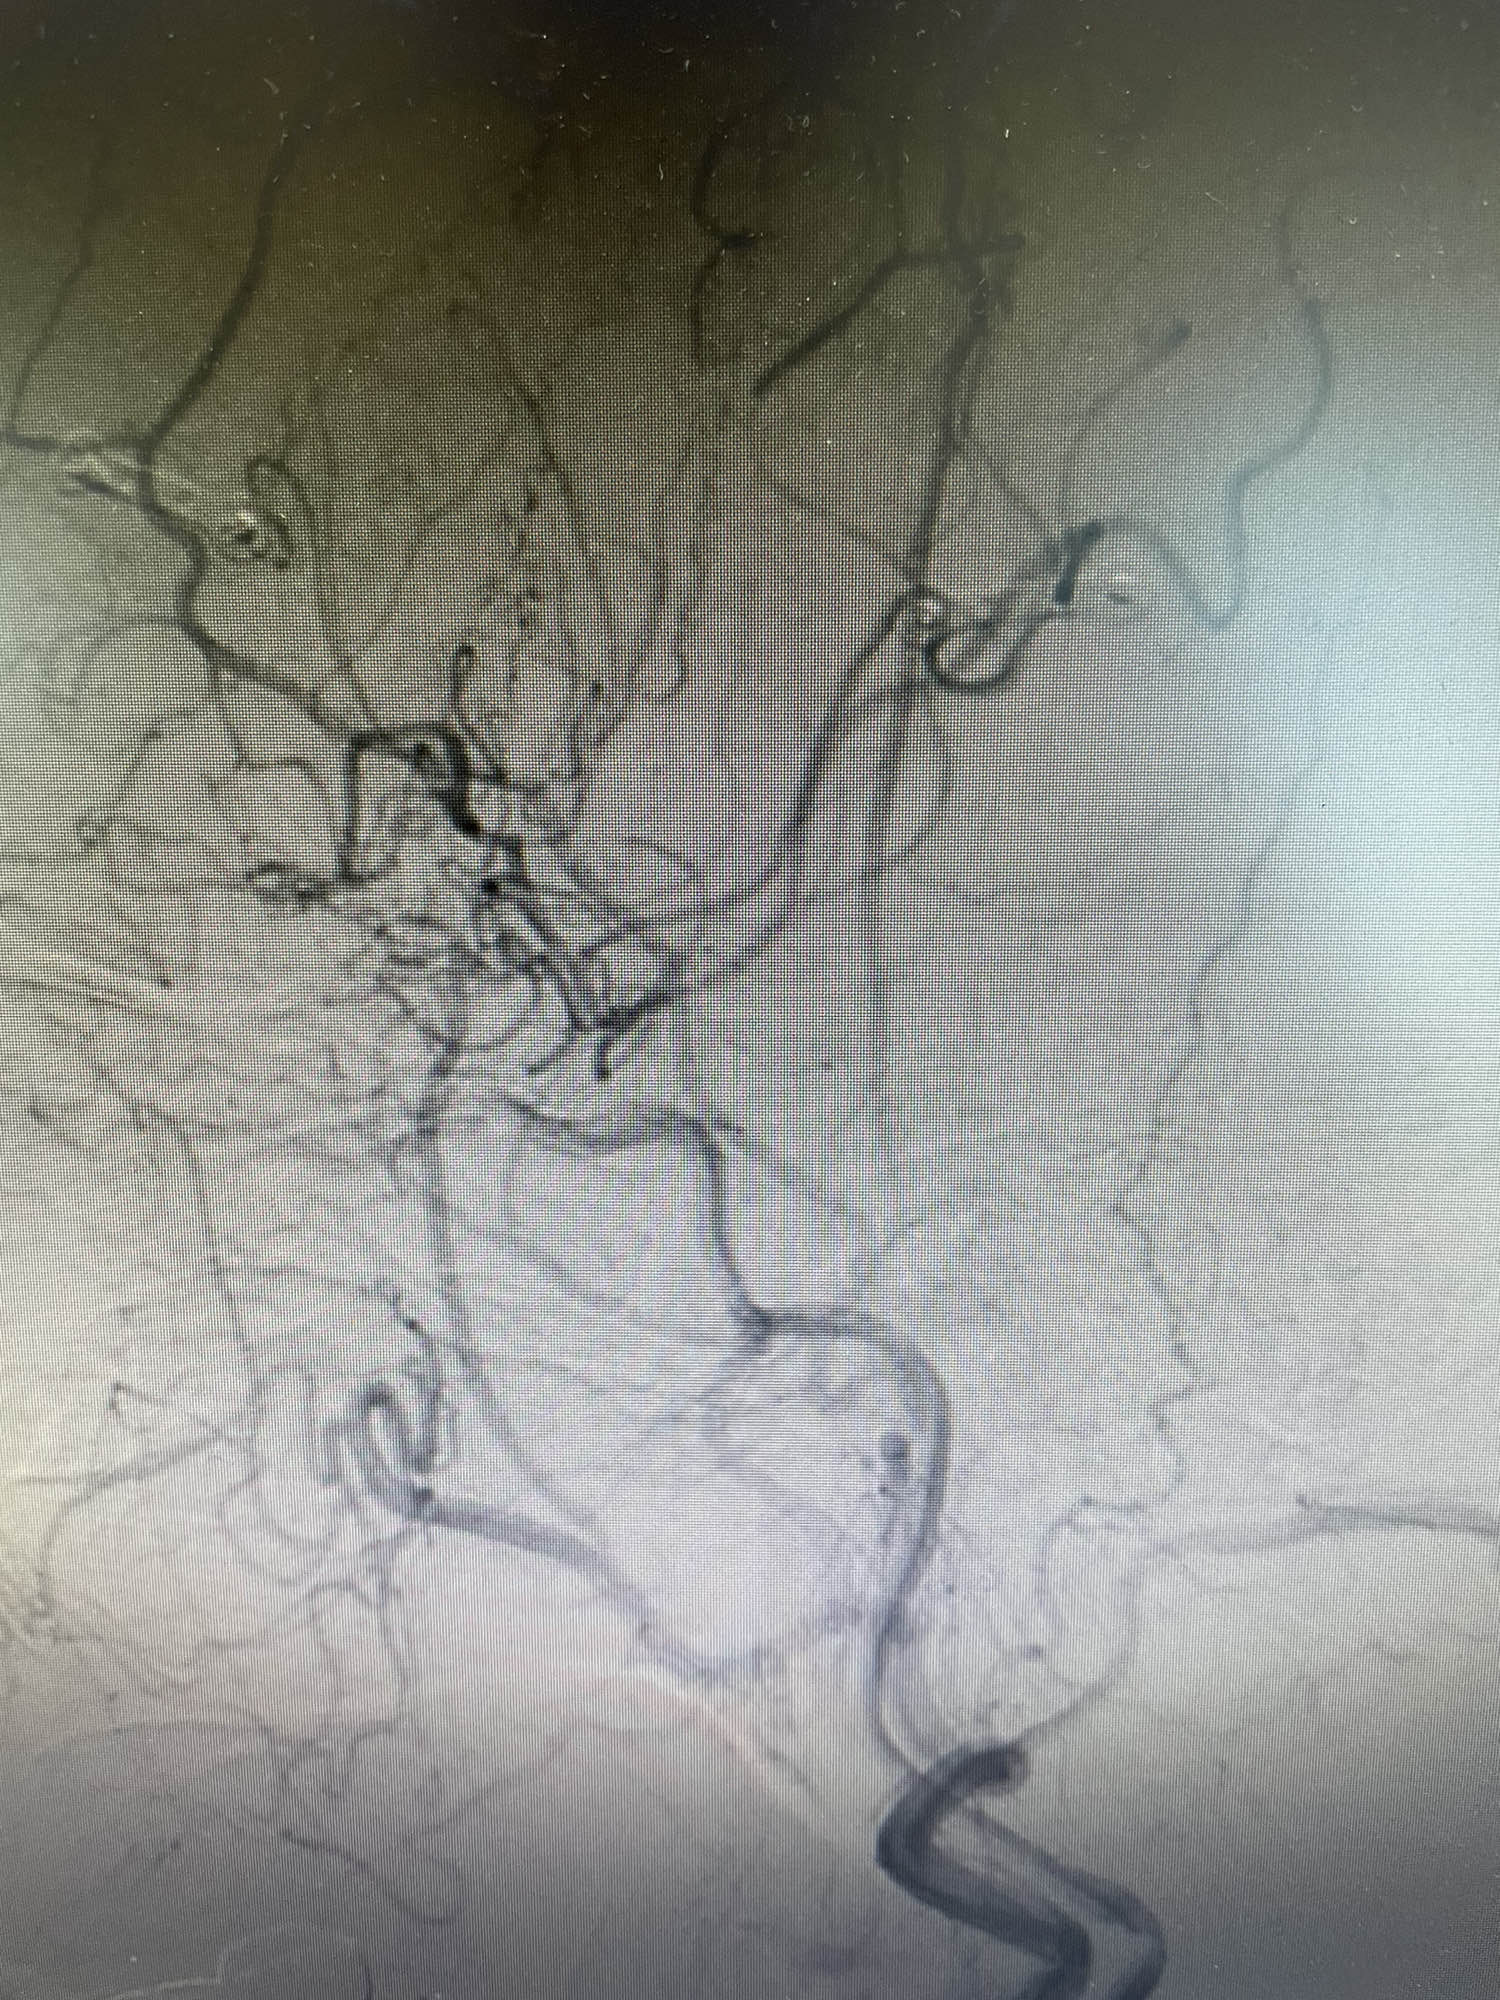

术前片子显示大脑中动脉闭塞